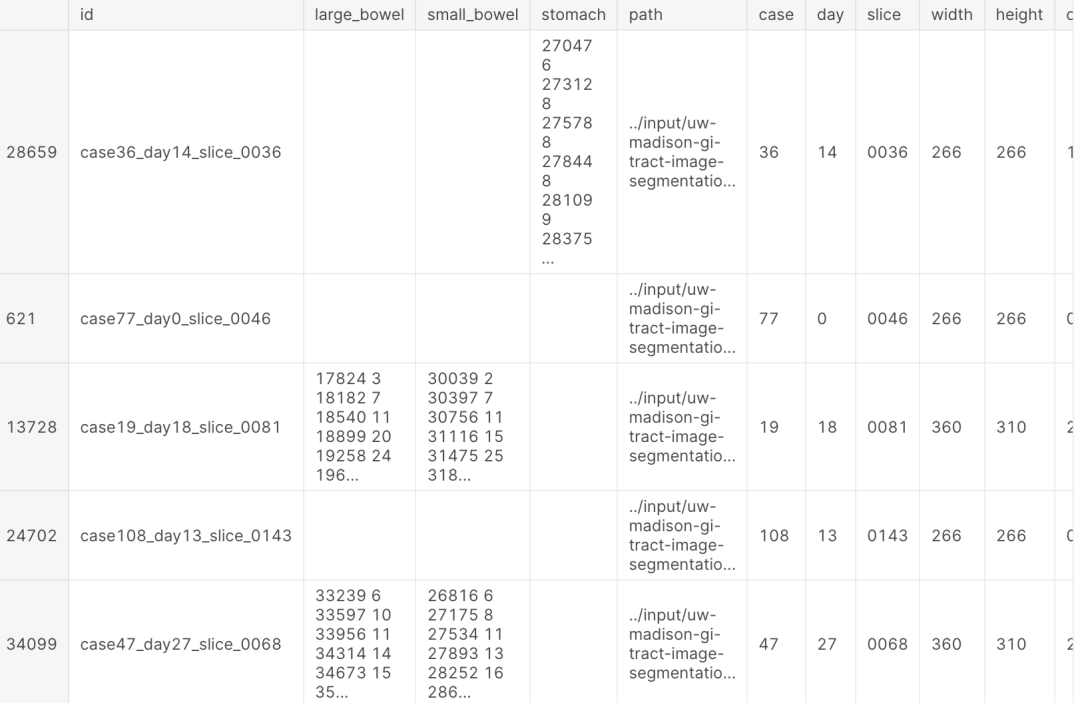

3、数据EDA

训练数据一览:

图像可视化: